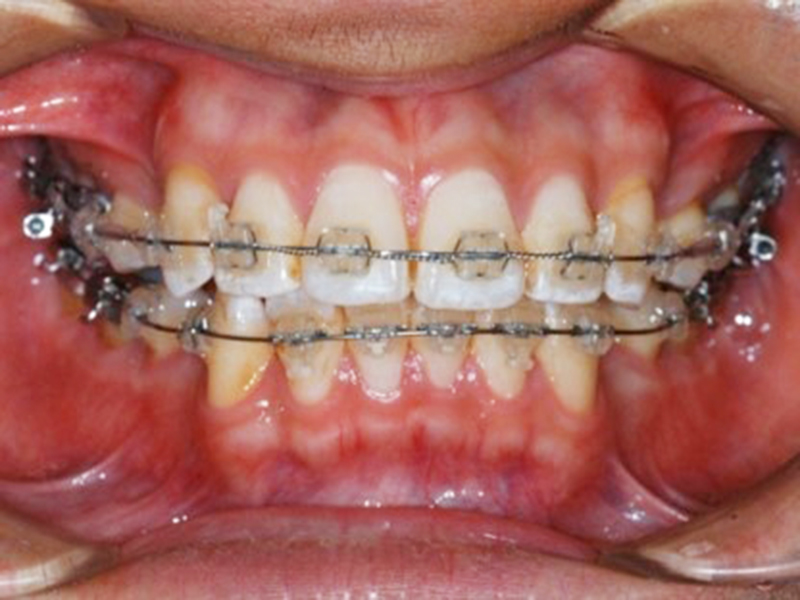

経過